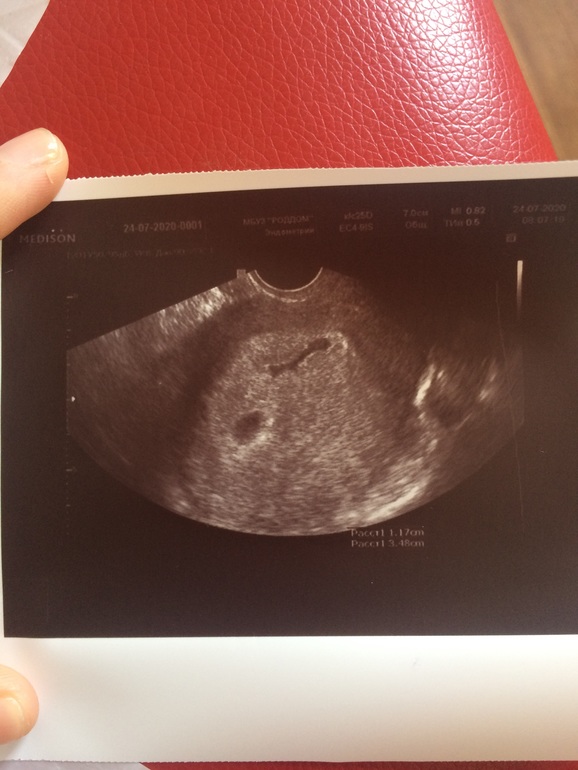

Дневник беременностиЭмбриона и сердцебиения пока не видно, ЖТ кистозное 28 мм (это меньше чем за 2 недели с 19 мм).

ВДПЯ 12 мм, Яйцо визуализируется, Локализация хориона - кольцевидная, Желточный мешок диаметром - 2 мм.

Срок беременности - 4 - 5 недель. Срок по ПДМ - 6 недель.